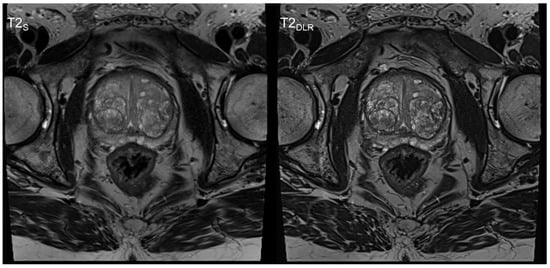

3.1. Image Quality Analysis

| T2S | Standard T2-weighted TSE imaging; |

| T2DLR | Deep learning reconstructed T2-weighted TSE imaging; |